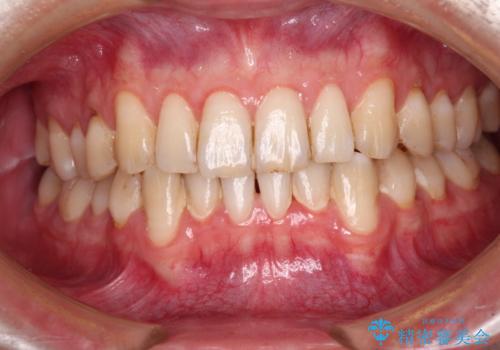

- 下顎犬歯の歯肉退縮を気にして来院された患者様です。

歯磨きの際にしみるとのことで、歯肉移植による根面被覆を行うこととしました。